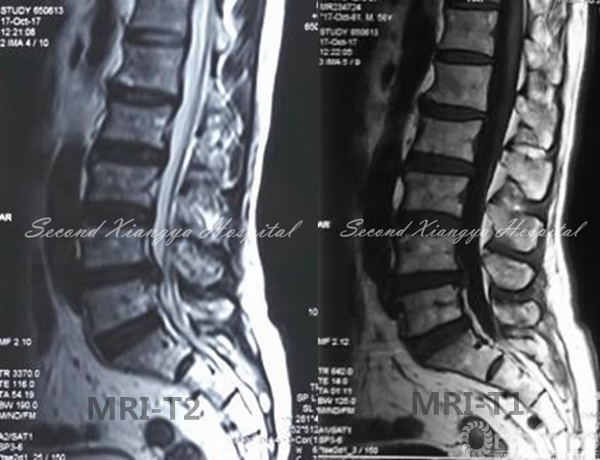

MRI:L4/5椎间盘右侧突出,非游离,无钙化,伴侧隐窝狭窄。

MRI-T2、MRI-T1

MRI-TRANSVERSE